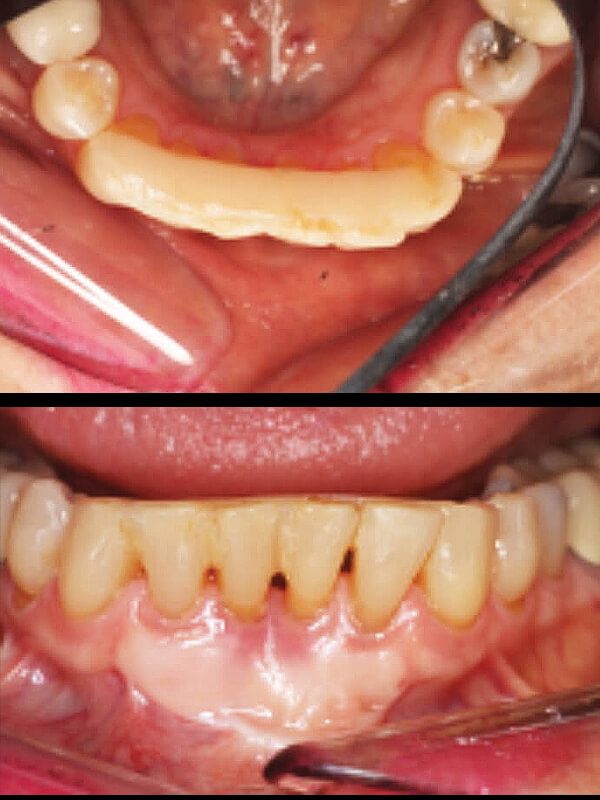

Splinting Loose Teeth:

Bone loss due to gum disease can lead to mobile or …“Loose teeth”! Loose teeth can interfere with chewing, and cleaning and if not corrected can accelerate existing gum disease, resulting in tooth loss. One simple and easy way to treat loose teeth is to “splint” loose teeth to their neighbor. In this fashion loose teeth can lean on stable teeth for support, sharing the workload of chewing. As a result, the bone and tissues can recover and return to health.